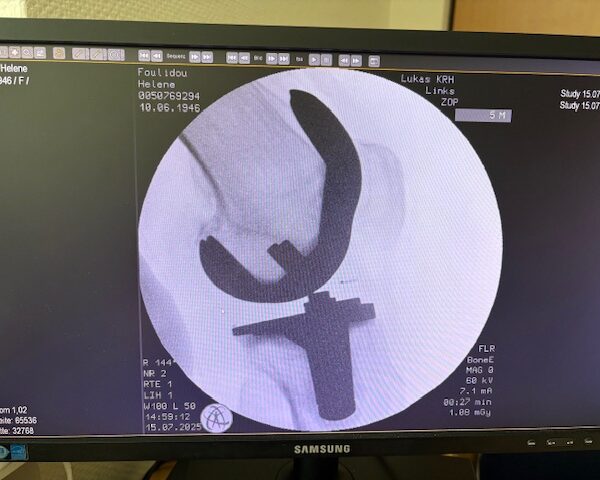

Η επέμβαση πραγματοποιήθηκε με ρομποτικά υποβοηθούμενη τεχνική, κατά την οποία το ρομποτικό σύστημα με καθοδήγησε με ακρίβεια χιλιοστού σε κάθε στάδιο.

Έτσι εξασφαλίστηκε η ιδανική τοποθέτηση των εμφυτευμάτων, η αποκατάσταση του μηχανικού άξονα και η διατήρηση των μαλακών ιστών.

Τα εμφυτεύματα που χρησιμοποιήθηκαν στο γόνατο της ασθενούς είναι της Aesculap: E-Motion Pro, μηριαίο μέγεθος 4, κνημιαίο μέγεθος 4, με ενθέμα (inlay) 10mm.